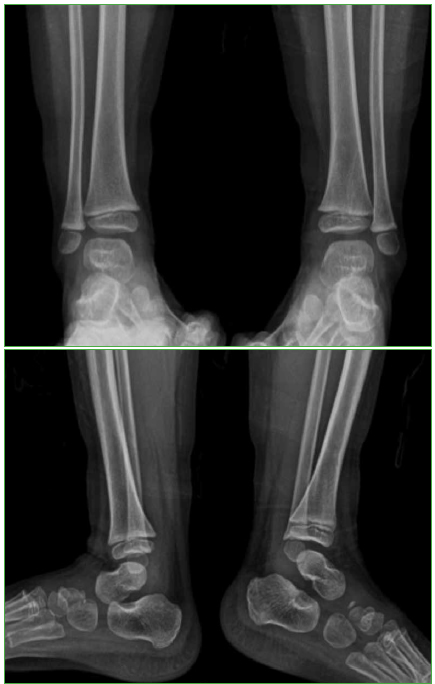

Clínicamente la paciente mostraba facie de dolor y llanto a la palpación del tercio distal de la pierna. Sin dolor a la movilidad pasiva del tobillo. No se observaron hematomas, edema, ni signos de flogosis local. Se solicitaron radiografías de ambos miembros inferiores, en las cuales se observó una lesión osteolítica que comprometía la metáfisis distal de la tibia izquierda (Figura 1).

Figura 1. Radiografías de frente y de perfil, de ambos tobillos. B y D. Se puede observar la lesión osteolítica en la metáfisis distal de la tibia izquierda.

La evolución de la paciente fue muy favorable, sin dolor, ni secuelas motoras, ni daño esquelético residual, sin compromiso de la fisis, ni del crecimiento del miembro. Se puede observar la evolución de la lesión ósea en los controles radiográficos posoperatorios (Figuras 3-5).

Radiografías de frente y de perfil, de ambos tobillos, al año de la intervención.

Radiografías de frente y de perfil, de ambos tobillos, a los dos años de la intervención.

Radiografías de frente y de perfil, de ambos tobillos, a los 2 años y 6 meses de la intervención.